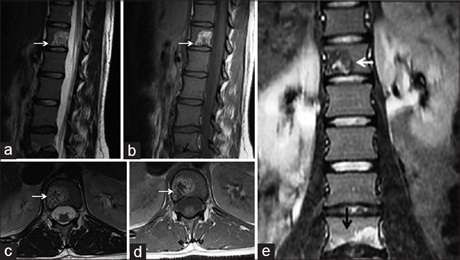

Cross-sectional Study on Incidental Spinal Findings in Magnetic Resonance Imaging Lumbar Spine of Patients with Low Back Pain

Dr. Binoj Varghese, Arun C Babu, Ashok Kumar, PS Priya, Jaison S John, Mohammed Noufal, KM Sivasubramaniyan (Author)

38-44

Magnetic Resonance Imaging of Lumbosacral Intervertebral Discs in Nigerians with Low Back Pain

Ademola Joseph Adekanmi, Temitope Olugbenga Bello , Dr. Omolola Mojisola Atalabi, Kamaldeen O Jimoh, Oluremi Ayotunde Ogunseyinde (Author)

61-67

Pattern of Lumbosacral Magnetic Resonance Imaging Findings in Diagnosed Cases of Disc Degenerative Disease among Nigerian Adults with Low Back Pain

Uzoamaka Rufina Ebubedike, Eric Okechukwu Umeh, Godwin I Ogbole, CA Ndubuisi, Wilfred C Mezue, Samuel C Ohaegbulam (Author)

25-29